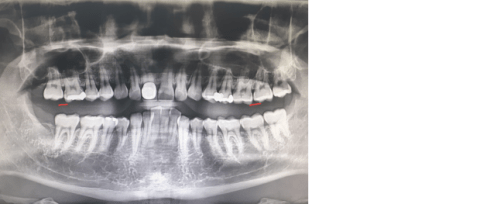

매복 사랑니 아닌데 발치 하려고 합니다.

제가 사랑니 아랫니 윗니가 있습니다. 매복이 아니고 정상적인 사랑니 이고 충치 크게 심하지 않은데 발치 하려고 합니다. 그 이유가 치실 할때 매우 불편 합니다. 발치 하려는데 아깝나요? 괜찮을까요? 사랑니 나중에 쓸모가 있습니까?

• 1번 째 사진

사랑니는 충치나 통증 등을 유발할 경우에는 반드시 발치가 필요하지만 관리가 잘 된다면 꼭 발치하지 않아도 됩니다. 하지만 관리를 아무리 잘 하여도 결국에는 문제가 생길 가능성이 높아 개인이 희망한다면 그냥 발치하여도 괜찮습니다. 나중에 별로 쓸모 있지도 않습니다.

사랑니의 경우 현재는 건강해도 장기적으로 보면 잘 닿지 않고다보니 치아가 상할가능성이 높습니다.

그렇기에 가능하면 뽑아주는 것이 좋습니다.

매복이 아니면 간단히 뽑을수있으므로 너무걱정마시고 뽑기바랍니다.